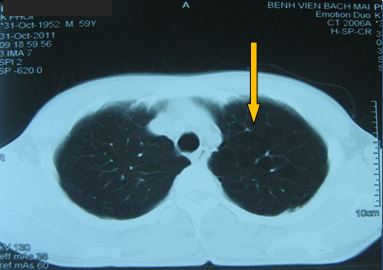

-          Bệnh nhân được tiến hành chụp cắt lớp vi tính ngực (CT ngực) đánh giá: có hình ảnh tổn thương toàn bộ thùy trên phổi trái

Hình ảnh tổn thương tái phát tương ứng với thùy trên phổi trái

+ Chụp CT ngực đánh giá sau 5 tháng điều trị:

Trước điều trị

Tổn thương ở vị trí thuỳ trên phổi trái: khối đông đặc và tổ chức u

Sau điều trị 5 tháng

Không rõ tổn thương